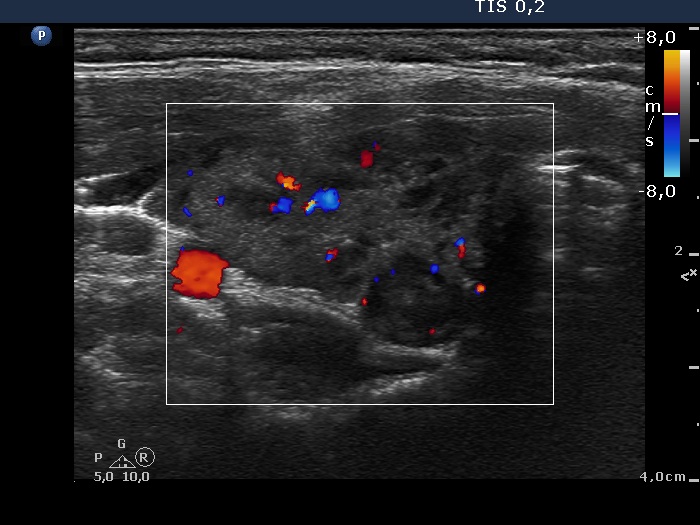

Discrete lesion or nodule in Hashimoto's thyroiditis - case 21 (1496) (ultrasonographic picture 3)

Right lobe, transverse view, color Doppler mode. The vascularization has no relevance in this case.